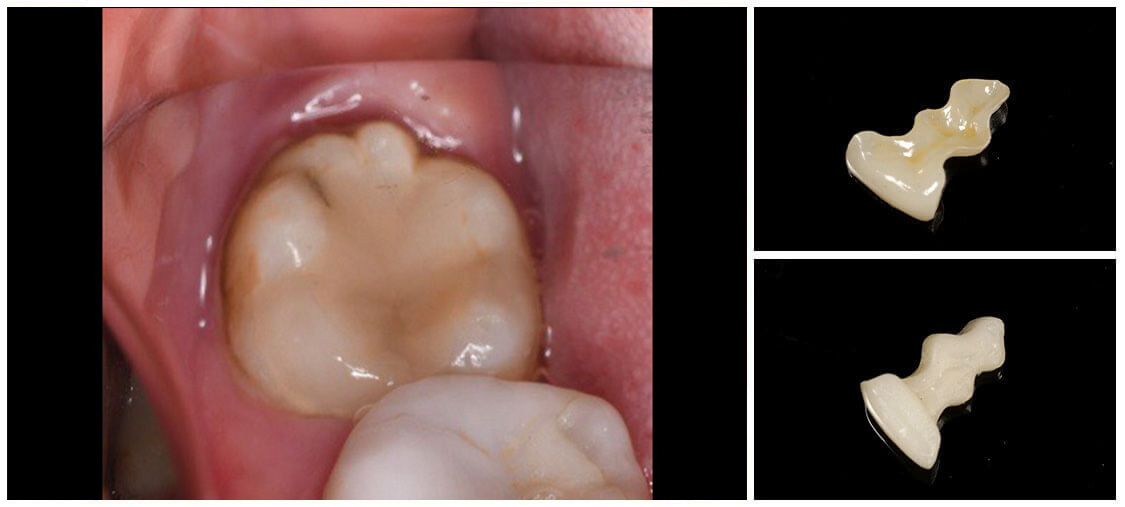

インレー

ジルコニアインレー・アンレー

セラミックインレー・アンレー

ゴールドインレー